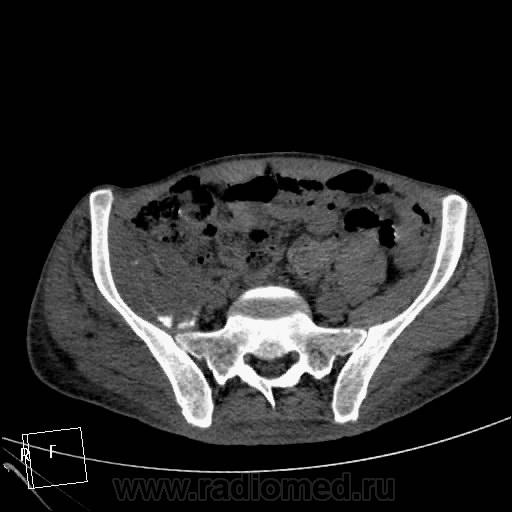

Мужчина 37 лет. Травму отрицает. Верификации нет, и неизвестно, будет ли. Думаю на остеосаркому. Характерно ли такое распространение до L3?

Лежал около месяца в другом ЛПУ, парез, отек конечности, преходящий парез другой конечности, худеет, слабость. К нам однократно в январе привозили на КТ головного мозга для исключения инсульта - исключили. Поступил вчера, в направлении "заболевание спинного мозга?", направлен на КТ грудного и поясничного отдела и таза для исключения мтс в позвоночник и перелом шейки правого бедра. В позвоночнике деструкции не нашла. Анализов пока тоже нет. Температура в норме.

ЗНАЧИТ ТАК - ТУТ ИМЕЕТ МЕСТО ПАТОЛОГИЧЕСКИЙ ПЕРЕЛОМОВЫВИХ В ОБЛАСТИ ПРОКСИМАЛЬНОГО ЭПИМЕТАФИЗА ПРАВОЙ БЕДРЕННОЙ КОСТИ !!САМ ПРОЦЕСС СКОРЕЕ ВСЕГО КАК С ОСТЕОЛИТИЧЕСКИМ ,ТАК И ОСТЕОБЛАСТИЧЕСКИМ КОМПОНЕНТОМ С ПРЕОБЛАДАНИЕМ 1-ГО.ИМЕЕТСЯ МЯГКОТКАННЫЙ КОМПОНЕНТОМ С УЧАСТКАМИ ПОНИЖЕННОЙ ПЛОТНОСТИ и обызвествлениями,разбросанными по периферии!!ПО ПЕРЕДНЕ ЛАТЕРАЛЬНОМУ КОНТУРУ ВЕРХНЕЙ ТРЕТИ ДИАФИЗА И МЕТАФИЗА БЕДРА ОПРЕДЕЛЯЕТСЯ ИГОЛЬЧАТЫЙ ПЕРИОСТИТ. В ПРОЕКЦИИ ЭПИМЕТАФИЗА ОПРЕДЕЛ-СЯ МНОЖЕСТВЕННЫЕ ФРАГМЕНТЫ РАЗНОЙ ДЕНСИМЕТРИЧЕСКОЙ ПЛОТНОСТИ/вдоль повздошных сосудов по задней и паравертебрально определяется инфильтрация восполительная или опухолевая.?местами ограниченные участки с низкой плотностью ,конгломерат увел лимфат -ких узлов ?с включениями извести в проекции крыла повздошной кости и повздшно поясничной мышцы.перелом патологич в области седалищной кости и крыши вертлужной впадины с остеолитическим компонентом ,в теле повздошной кости участок деструкци и со склеротической каймой !!

Почти... не со всем согласна, игольчатого периостита не нашла, но пересмотрю непременно. Переломовывих... ну есть укорочение конечности на 5 см, так ведь от головки бедра ничего не осталось, деструкция и вертлужной впадины, линии перелома как таковой и нет. А нет головки и вертлужки, тогда тоже вывих? Я не придираюсь, я понять хочу. И что в итоге? Как бы вы написали в заключении?

мой диагноз ходросаркома ,которая в отличие от остеосаркомы часто встречается в метаэпифизе бедренной кости+возраст 37лет тоже в пользу 1 ой.на счет перелома он патологический !!!даже если на данный момент нет шейки и головки !просто странно что только сейчас к вам направляют на потдверждение перелома .на счет вывиха даже в случае полного разрушения верхняя треть диафиза не там где нужно,смещена латерально и кзади ,на счет игольчатого периостита ,это конечно мое мнение пересмотрите 5срез в аксиальном костном режиме и 2 во фронтальном .и кстати на пятом в просвете прямой кишки определяется экзофитно растущее образование ? скорее всего это какашка извиняюсь за выражение но все же перепроверте может и то что мне кажется)))))ну и не нравится зона в проекции повздошно поясничной,повздошной и большой поясничной мышц с включениями извести и сниженной денситометрической плотностью ограниченных участков в центре .это может поменять диагноз первичного поражения мышц (саркома ) на кость вторично!предлагаю законтрастировать кишечник и сделать контрастное исследование (болюс)и посмотреть -что за природа этого участка .?